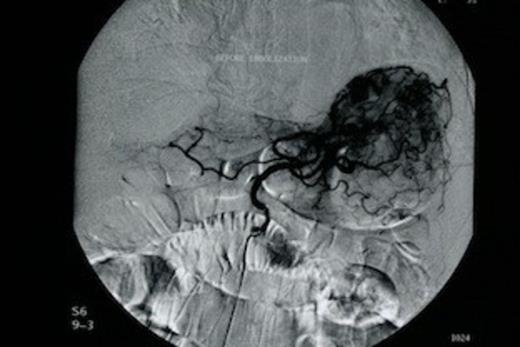

The patient was subjected to emergency oesophago-gastroduodenoscopy, which revealed extensive angiodysplasia of the gastric body. At first, conservative management was attempted with intravenous fluids and transfusions. After initial stabilization of the patient (Ht: 32.5%, 90bpm, 110/50mmHg), rebleeding was encountered within 48 hours and therefore decision for interventional radiology, embolization of the angiodysplasia, was made. Urgent angiography of the left gastric artery revealed extravasation of contrast material from the gastric body (Figure 1). Following that, successful arterial coil embolization, using super selective catheterization was achieved in the distal and proximal parts of the ruptured vessel (Figure 2). Consequently the patient recovered from the hemorrhagic shock.

Successful arterial coil embolization, using super selective catheterization in the distal and proximal parts of the ruptured vessel